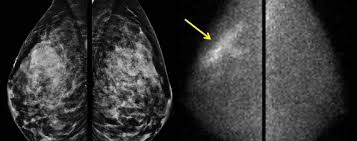

X Ray Mammogram Showing Evidence Of Breast Cancer Stock Image M122 0050 Science Photo Library from media.sciencephoto.com But it's not uncommon that they see something that looks like it might be cancer —a finding that could end up being completely normal, but that needs to be further tested to be sure. What does cancer look like on a mammogram? The tumor cells don't stay within the clear borders of the mass, but instead invade the nearby breast tissue. This type of cancer also changes the appearance of your breasts. This can make it harder for your radiologist to spot signs of breast cancer, since dense tissue and tumors both look white in mammogram images. The look of breast cancer on a mammogram a tumor or lump will appear as a focused white area on the mammogram. A mammogram can show breast changes such as calcifications, masses, or other symptoms that might be cancer. Dr sarah jarvis mbeif a mammogram is abnormal, further tests will be needed.

Invasive breast cancer can appear as a white patch or mass on a mammogram. The tumor cells don't stay within the clear borders of the mass, but instead invade the nearby breast tissue. You may notice dimpling or pitting, and the skin on your breast. A rash isn't the only visual symptom of inflammatory breast cancer. Regular mammograms are the best tests doctors have to find breast cancer early. In a normal breast, a mammogram shows normal skin dark grey fat and lighter grey breast tissue. According to the american cancer society (acs), the most common sign of breast cancer is a new lump or mass in the breast. How can mammograms be used? Cancers may be seen as masses (like a ball, but usually with an irregular shape), areas of asymmetry that resemble normal tissue, calcifications (white specks), and/or areas of architectural distortion (imagine the puckering caused by pulling a thread in a piece of fabric). In this mammogram image, the breast calcifications are in ductal patterns. Healthy mammograms can still vary in appearance. It is important to bear in mind that most women who are asked to come back after. Any area that does not look like normal tissue is a possible cause for concern.

Ibc symptoms are caused by cancer cells blocking lymph vessels in the skin causing the breast to look inflamed. symptoms include breast swelling, purple or red color of the skin, and dimpling or thickening of the skin of the breast so that it may look and feel like an orange peel. What does cancer look like on a mammogram? Cancers may be seen as masses (like a ball, but usually with an irregular shape), areas of asymmetry that resemble normal tissue, calcifications (white specks), and/or areas of architectural distortion (imagine the puckering caused by pulling a thread in a piece of fabric). Tumors may be benign or cancerous. According to the american cancer society (acs), the most common sign of breast cancer is a new lump or mass in the breast. Suspicious findings include clusters of tiny microcalcifications or a density/mass with irregular or spiculated margins. Any area that does not look like normal tissue is a possible cause for concern. This can make it harder for your radiologist to spot signs of breast cancer, since dense tissue and tumors both look white in mammogram images. Breast cancer and some noncancerous (benign) breast conditions can appear white on a mammogram. This is considered an abnormal mammogram, but not necessarily one that's indicative of cancer. Invasive breast cancer can appear as a white patch or mass on a mammogram. By the time it's diagnosed, it usually has grown into the skin of your breast. What does an abnormal mammogram look like?

Ai Assisted Radiologists Can Detect More Breast Cancer With Reduced False Positive Recall Imaging Technology News from www.itnonline.com Breast cancer and some noncancerous (benign) breast conditions can appear white on a mammogram. By the time it's diagnosed, it usually has grown into the skin of your breast. The outer edges of these cells look fuzzy or spiky (called spiculated). They will look carefully at the mammogram to interpret the results. The doctor reading your mammogram will be looking for different types of breast changes, such as small white spots called calcifications, larger abnormal areas called masses, and other suspicious areas that could be signs of cancer. The appearance of normal breast tissue on a mammogram varies from person to person, and no two mammograms look the same. Cancers may be seen as masses (like a ball, but usually with an irregular shape), areas of asymmetry that resemble normal tissue, calcifications (white specks), and/or areas of architectural distortion (imagine the puckering caused by pulling a thread in a piece of fabric). According to the american cancer society (acs), the most common sign of breast cancer is a new lump or mass in the breast.